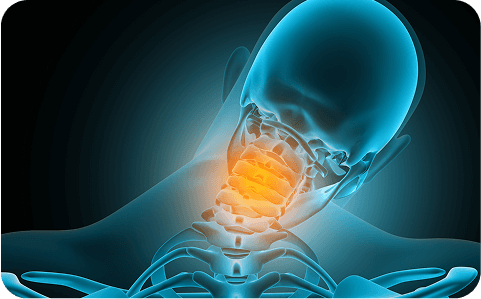

Stiffness, posture strain, facet pain when turning or looking down.

Migraine, tension, or cervicogenic headaches; occipital nerve blocks clarify the source.

Post-impact stiffness, muscle spasm, and loss of range of motion.

Arm pain, tingling, or weakness from compressed nerve roots.

Disc bulge or rupture pressing nerves; treated with epidurals and micro-decompression.

Canal narrowing leading to hand clumsiness, leg heaviness, or unsteady gait.